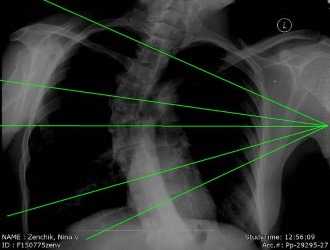

Для предупреждения вероятности затенения позвонков внутренними органами снимки делают в 2 проекциях: прямой и боковой. Обследование длится несколько минут. Во время его проведения пациент должен лежать неподвижно.

Обычно рентген грудного отдела делают в двух проекциях